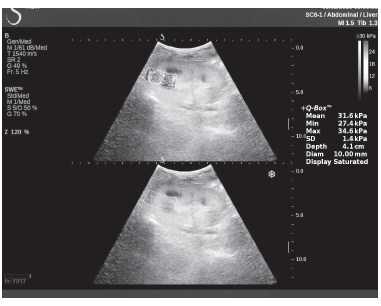

Клинический пример из второй группы. Пациент К. перенес операцию пересадки почки от живого родственного донора. Трансплантат в левой подвздошной области. Индекс резистентности в междольковых артериях составил 0,70 (рис. 5). В сегментарных артериях индекс резистентности составил 0,66 (рис. 6). Показатели жесткости паренхимы почечного трансплантата при режиме УЭСВ составили от 31,6 до 36,9 кПа (рис. 7-9).

Рисунок 9. Исследование в режиме ультразвуковой эластографии сдвиговой волны у пациента К.: жесткость паренхимы у верхнего полюса почечного трансплантата 31,6 кПа